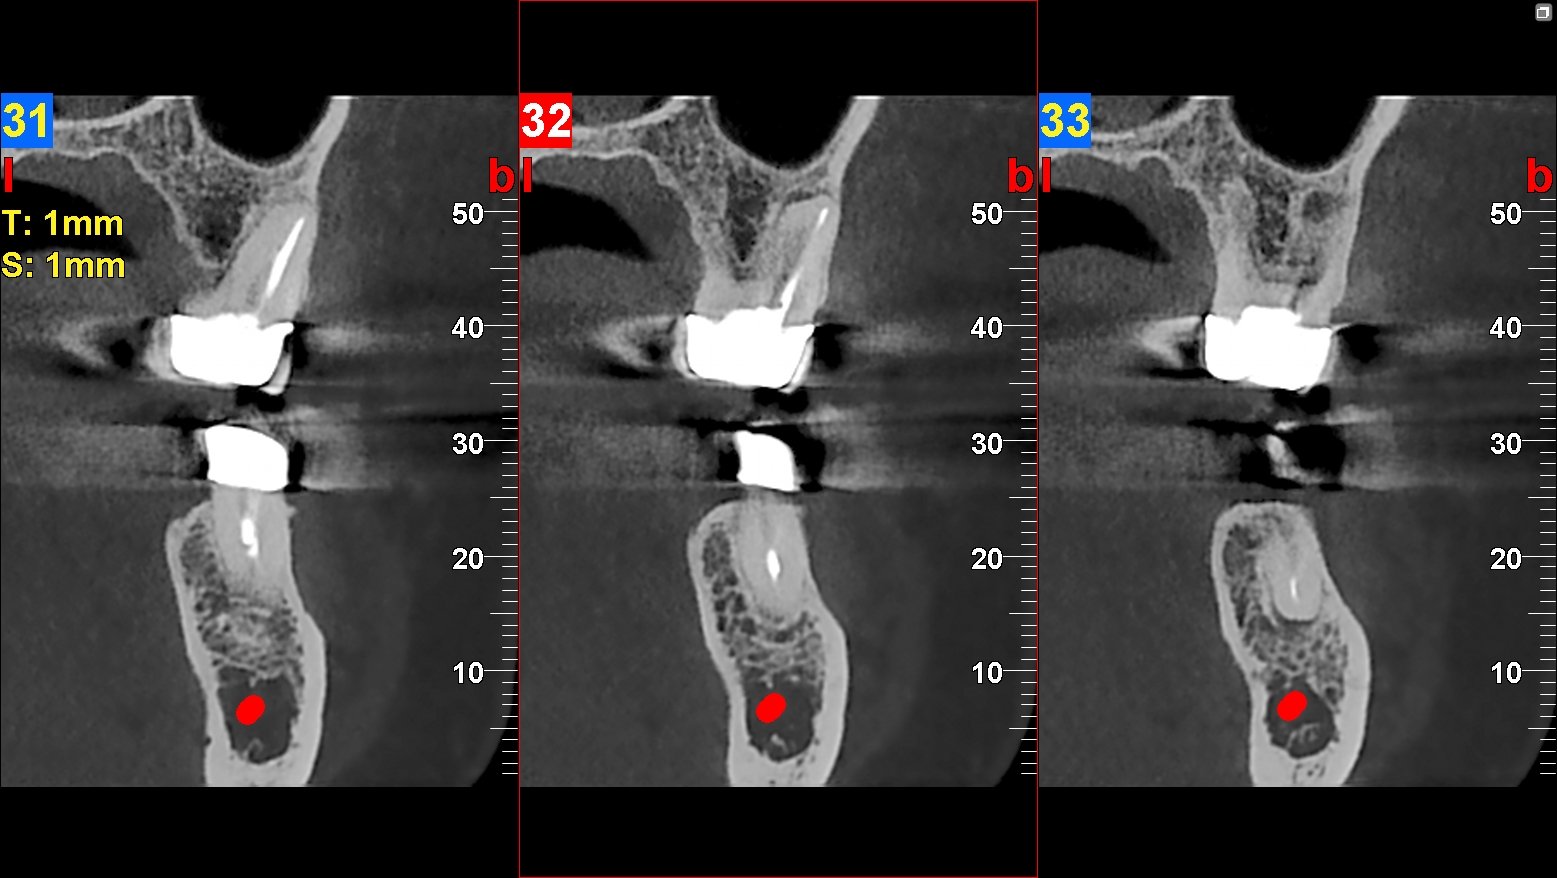

La radiología facial se refiere al uso de técnicas de imagen para examinar las estructuras faciales y cráneo-faciales. Esto incluye radiografías, tomografías computarizadas (TC) y resonancias magnéticas (RM), cada una con sus propias aplicaciones y ventajas. La radiografía convencional utiliza rayos X para crear imágenes bidimensionales, mientras que la TC proporciona imágenes en cortes transversales del área examinada, lo que permite una visualización más detallada de las estructuras internas.

Por otro lado, la resonancia magnética utiliza campos magnéticos y ondas de radio para generar imágenes de alta resolución, especialmente útiles para evaluar tejidos blandos. El proceso de obtención de imágenes faciales generalmente comienza con la preparación del paciente, que puede incluir instrucciones sobre cómo posicionarse adecuadamente. Una vez en posición, se aplica una pequeña dosis de radiación (en el caso de las radiografías) o se coloca al paciente en un escáner (en el caso de TC o RM).

Las imágenes resultantes son analizadas por radiólogos o médicos especialistas, quienes interpretan los hallazgos y emiten un informe que puede ser utilizado para guiar el tratamiento.

Otro hallazgo común es la presencia de infecciones dentales que pueden extenderse a otras áreas del cuerpo si no se tratan adecuadamente. Estas infecciones pueden manifestarse como áreas oscuras en las radiografías, lo que indica pérdida ósea o abscesos. La identificación temprana de estos problemas es crucial para evitar complicaciones más graves que puedan afectar la salud general del paciente.

Los senos paranasales son cavidades llenas de aire ubicadas en el cráneo que pueden verse afectadas por diversas condiciones patológicas. La radiología facial es esencial para evaluar estos espacios y detectar problemas como sinusitis aguda o crónica. A través de radiografías específicas o tomografías computarizadas, los médicos pueden observar inflamaciones o bloqueos en los senos paranasales que podrían estar causando síntomas como congestión nasal o dolor facial.

Además, las imágenes pueden revelar anomalías estructurales como pólipos nasales o desviaciones del tabique nasal que podrían contribuir a problemas respiratorios. La identificación precisa de estas condiciones permite a los médicos planificar tratamientos adecuados, ya sea mediante medicamentos o intervenciones quirúrgicas. En este sentido, la radiología facial se convierte en una herramienta indispensable para abordar problemas relacionados con los senos paranasales.